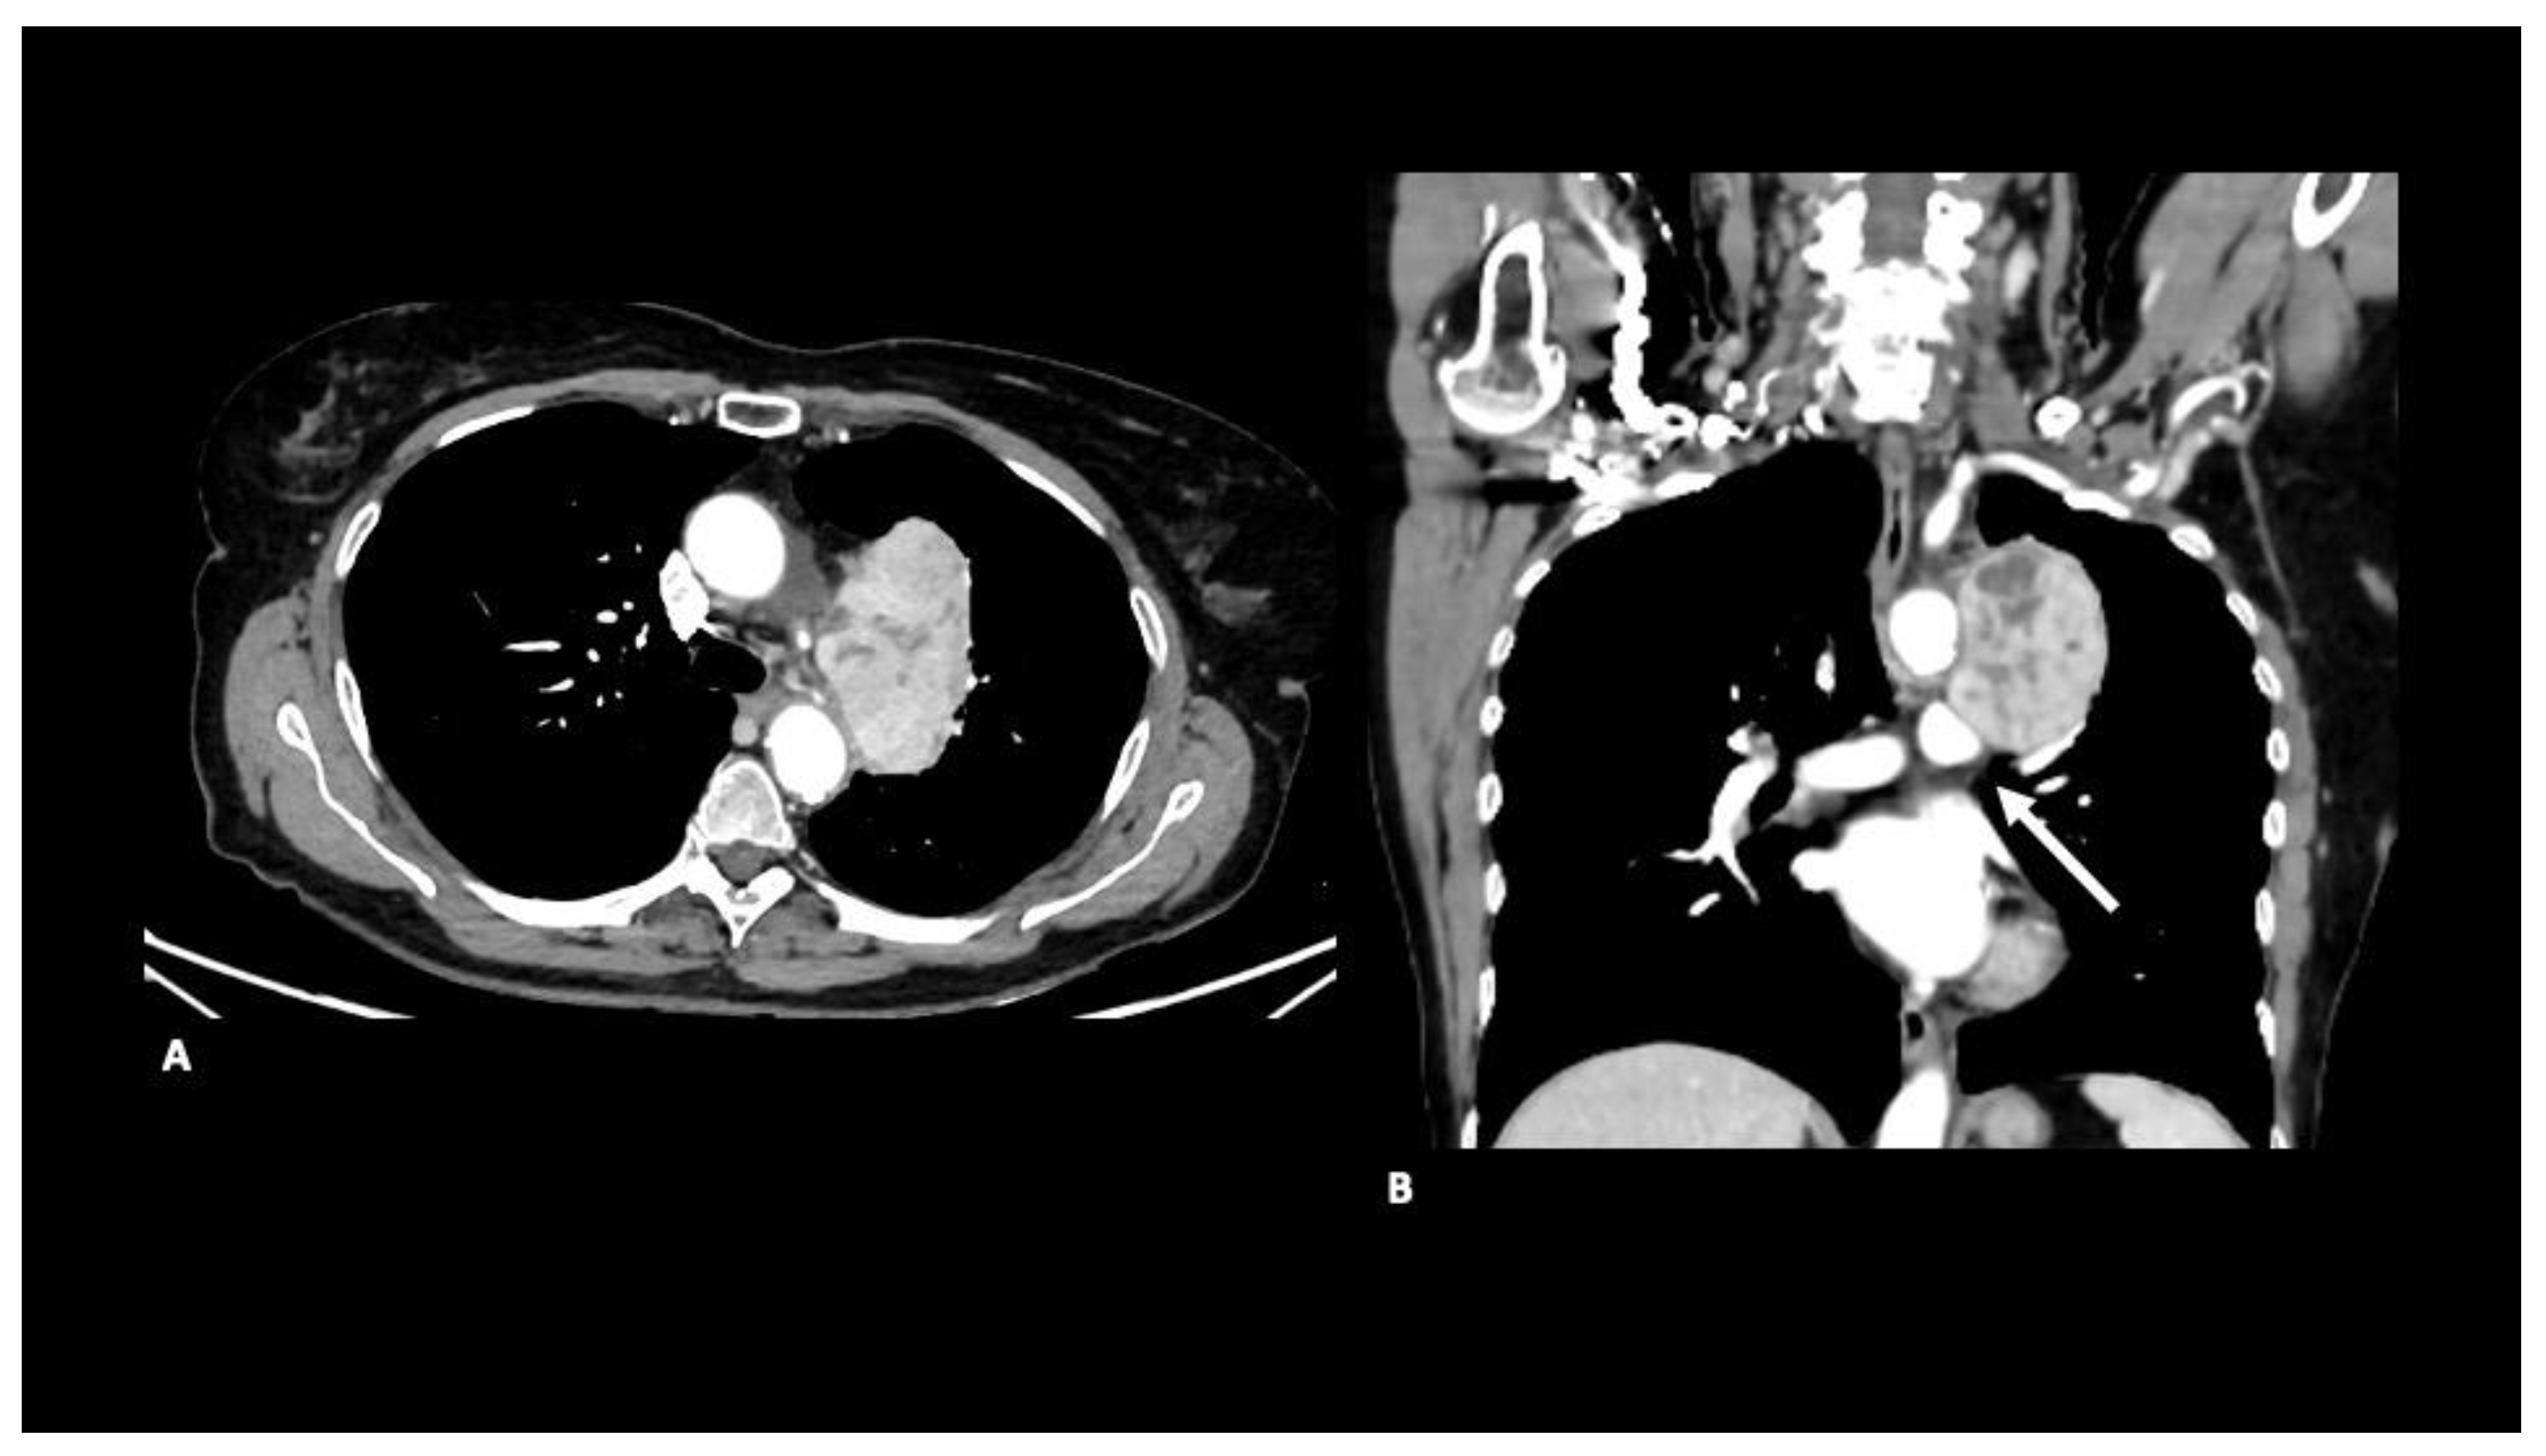

A contrast-enhanced CT scan showed a large, heterogeneous mass extending into the aortopulmonary window and compressing the left pulmonary artery (Figure 1).

Figure 1. Axial (A) and coronal (B) contrast-enhanced CT images show a large, heterogeneous mediastinal mass that extends into the aortopulmonary window and compresses the left pulmonary artery. Note the large size and the heterogeneous attenuation, standard features of leiomyosarcoma.